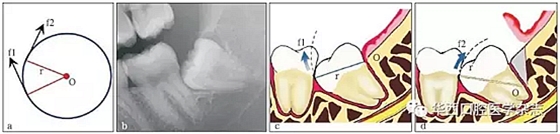

3.3.1 轉(zhuǎn)動(dòng)軸心與圓弧運(yùn)動(dòng) 這一原理在前傾或水平阻生智齒的拔除中運(yùn)用最廣??梢酝ㄟ^(guò)改變牙體轉(zhuǎn)動(dòng)脫位時(shí)的運(yùn)動(dòng)軸心,來(lái)改變牙體上各點(diǎn)的運(yùn)動(dòng)方向(圖 4),從而避開(kāi)阻力而使牙齒脫位。但在此過(guò)程中,牙槽窩的擠壓變形仍不可避免。尤其是舌側(cè)骨板的骨折,更是經(jīng)常發(fā)生的事件。要進(jìn)一步減少對(duì)牙槽窩的擠壓,則需要對(duì)牙根進(jìn)行進(jìn)一步的切割。

在圓周運(yùn)動(dòng)(旋轉(zhuǎn))中,圓周上所有點(diǎn)的運(yùn)動(dòng)方向(f1、f2)均為切線方向,與通過(guò)該點(diǎn)的半徑(r)相垂直(圖a)。當(dāng)牙齒發(fā)生旋轉(zhuǎn)脫位時(shí),其阻力點(diǎn)的運(yùn)動(dòng)方向會(huì)隨著轉(zhuǎn)動(dòng)的軸心點(diǎn)的變化而變化,從而避開(kāi)阻力。前傾阻生智齒(圖b)脫位時(shí),阻力分析如圖 c所示,因阻力點(diǎn)位于旋轉(zhuǎn)中心(O)的下方,旋轉(zhuǎn)脫位時(shí),其阻力點(diǎn)的運(yùn)動(dòng)方向(f1)是向前上的,被鄰牙所阻擋。如果按照?qǐng)D d所示,去除遠(yuǎn)中骨質(zhì)(灰色部分)或切割牙體(r)后,旋轉(zhuǎn)中心(O)下移,阻力點(diǎn)的運(yùn)動(dòng)方向就改變?yōu)橄蚝笊希╢2),而得以避開(kāi)鄰牙阻擋而脫位。

圖4 轉(zhuǎn)動(dòng)軸心與圓弧運(yùn)動(dòng)